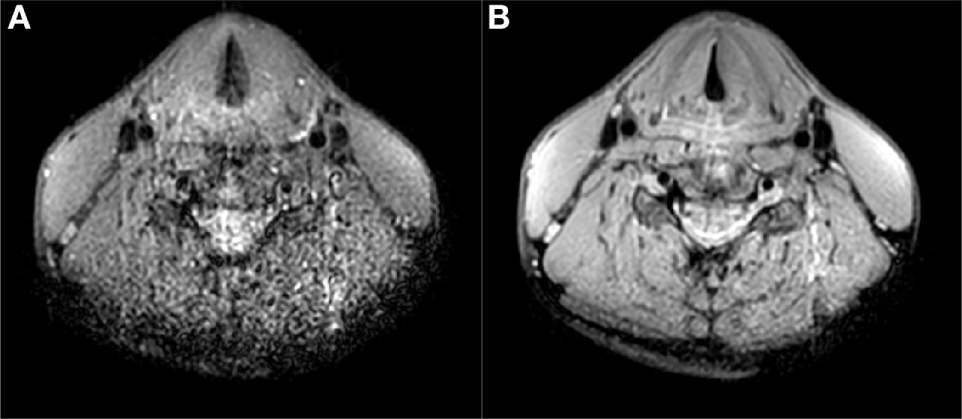

A 64-year-old male patient presented with a carcinoma of the left vocal cord with involvement of the anterior commissure and the anterior part of the contralateral vocal cord (T1b). Because of limited endoscopic exposure of the larynx, TLM could not be performed and the patient was treated with RT (25 fractions of 2.4 Gy each). Due to anxiety disorder, the patient refused flexible laryngoscopy during follow-up. For further surveillance, an MRI examination of the larynx was requested 8 months after irradiation. A subsection of the images acquired using the new coil and imaging protocols are shown in Figure 6. On T2-weighted images without and with fat suppression increased signal intensity was seen in both vocal cords and an area with intermediate signal on the surface of the left vocal cord (Figures 6A,B). On DWI, the T2 hyperintense areas showed no diffusion restriction, corresponding to inflammatory edema. DWI showed diffusion restriction in the superficial portion of the left vocal cord, compatible with submucosal recurrence (Figures 6C,D). In this patient, slowly increasing enhancement was seen and in tumor recurrence enhancement has been reported to be variable (8) (Figures 6E,F). Histopathological examination of biopsy specimens from the left vocal cord confirmed the presence of squamous cell carcinoma.

Figure 6

Magnetic resonance imaging scans 8 months after radiation therapy for a T1b glottis carcinoma. Increased signal intensity on T2-weighted scans without (A) and with (B) fat suppression in both vocal cords, together with the absence of diffusion restriction on DWI/ADC (C,D) is compatible with posttreatment edema. A biopsy in the superficial area corresponding to intermediate signal on T2 and diffusion restriction on the left vocal cord revealed tumor recurrence. Contrast-enhanced T1-weighted scans at two different time points show gradual enhancement (E,F).